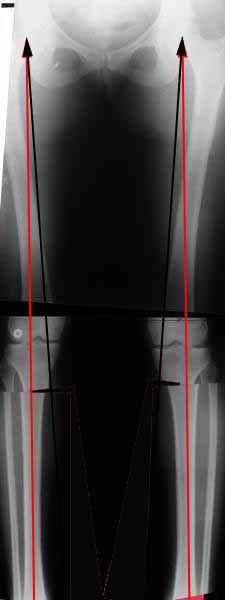

AVM> Александр, а не могли бы вы представить ваши схемы расчета? С учетом

Вот, с учетом и без учета, и на разных уровнях...

Саша Артемьев, может, для данного случая свой вариант нарисуешь?